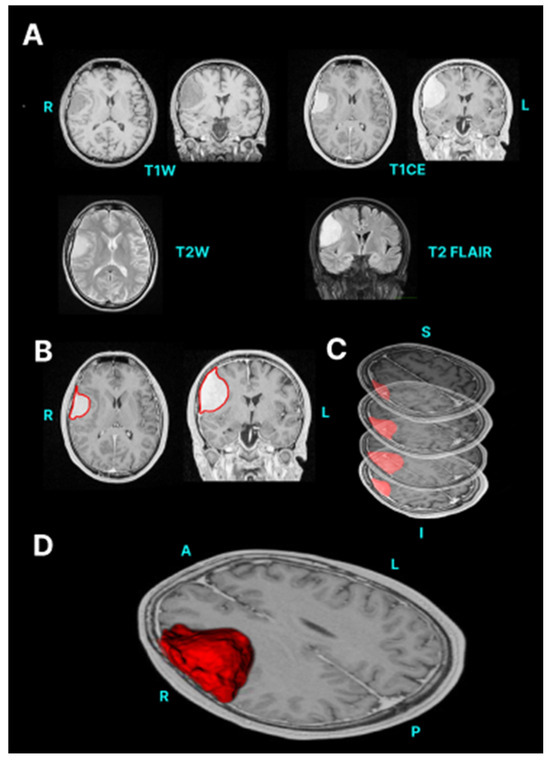

| Meningioma | T1w T1w + contrast T2w | Meningiomas have isointensity to slight hypointensity with T1 weighting. With T2-weighted sequences, meningiomas have isointensity to slight hyperintensity [32]. Two basic morphologies of meningioma include en plaque with a sheet-like dural extension and globose with a broad dural attachment [33]. The thick extended dura (commonly referred to as a dural tail) tends to extend away from the meningioma, which can be easily missed [34]. Bone changes may be visible, such as hyperostosis, osteolysis, enlargement of the skull base foramina and meningioma calcification [35]. |